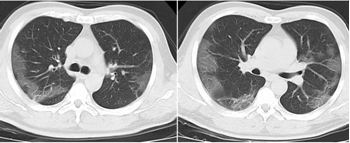

3.胸部影像學(xué)表現(xiàn)

早期呈現(xiàn)多發(fā)小斑片影及間質(zhì)改變,以肺外帶明顯。進(jìn)而發(fā)展為雙肺多發(fā)磨玻璃影、浸潤(rùn)影,嚴(yán)重者可出現(xiàn)肺實(shí)變,胸腔積液少見(jiàn)。

外周散在多發(fā)小斑片影

支氣管、血管束增粗

雙肺多發(fā)GGO

重癥患者,雙肺呈彌漫性病變,以實(shí)變影為主,合并GGO